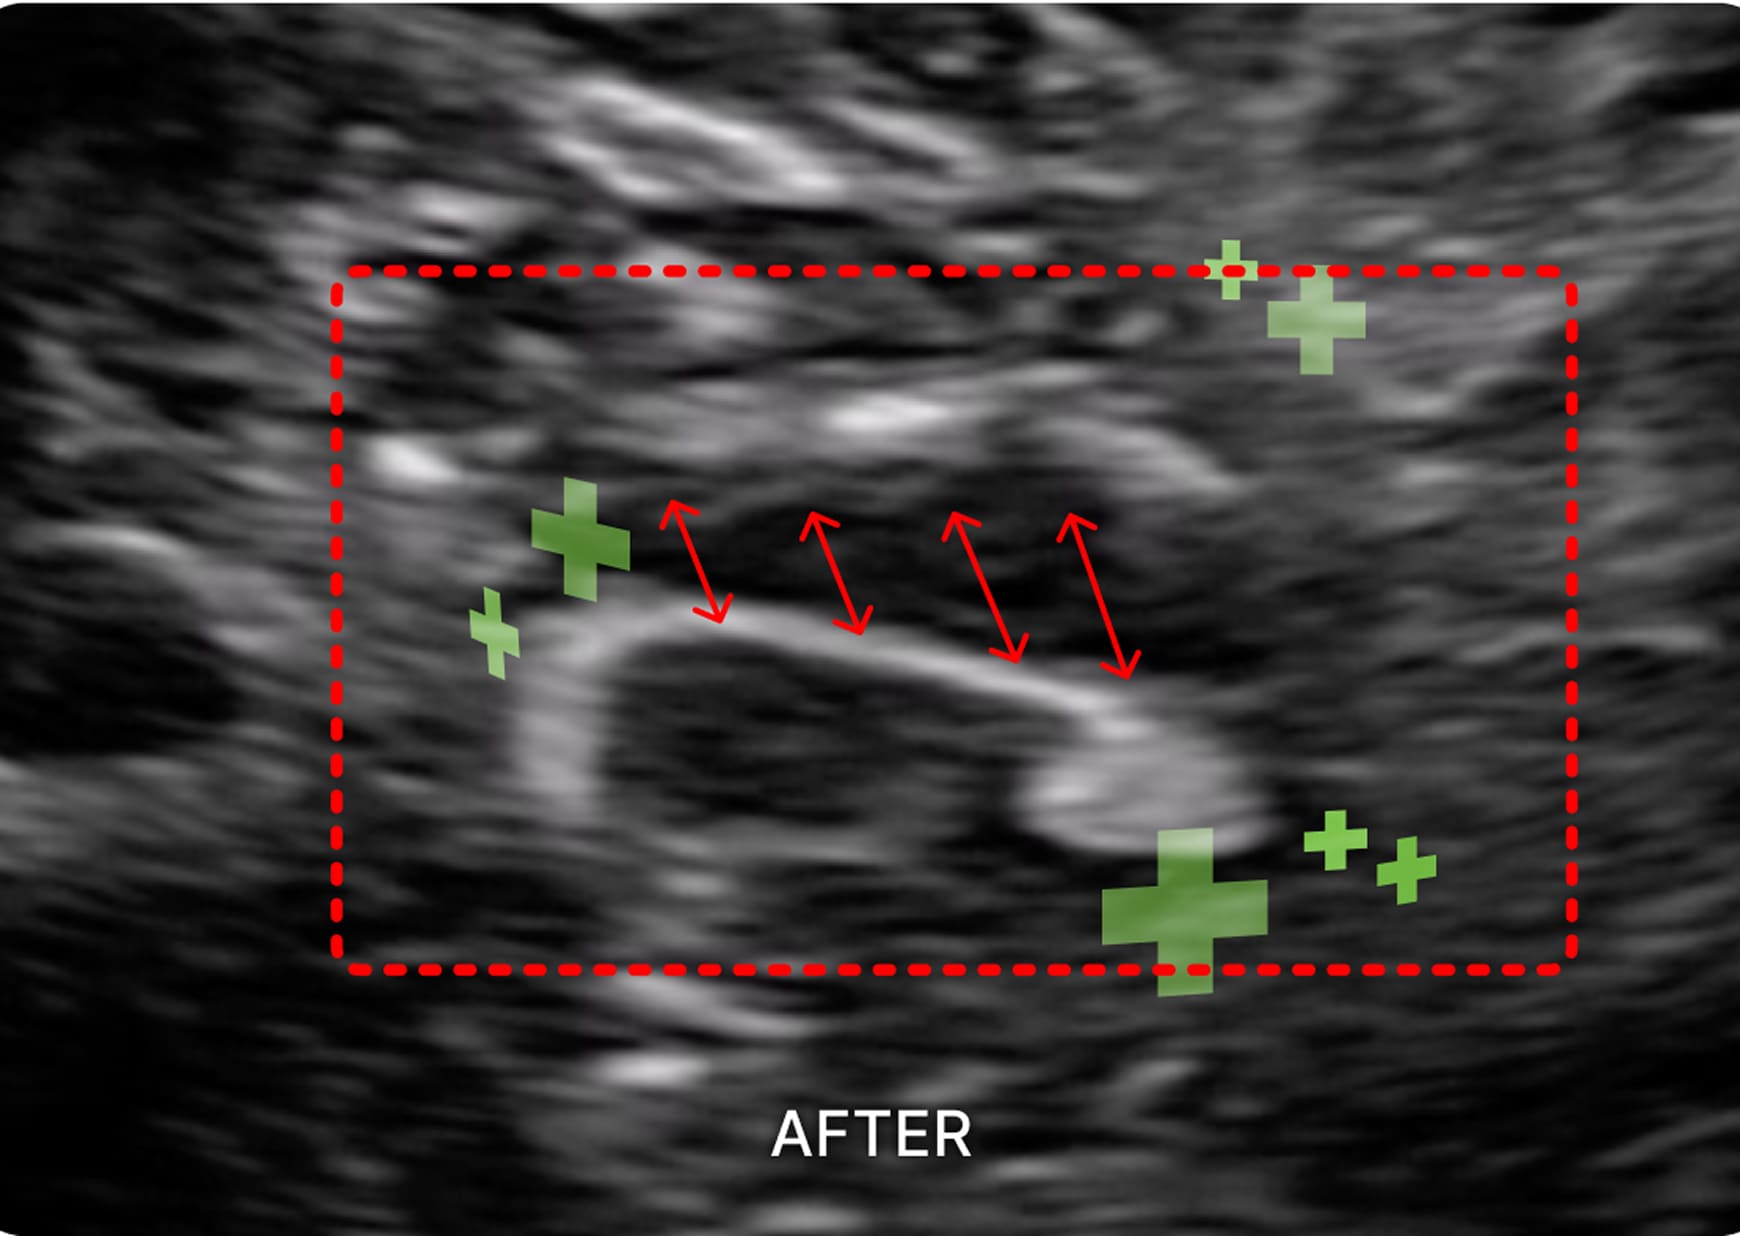

1. 초음파 시술

초음파를 활용하여 근육과 신경 문제를

정확히 진단하고 치료하여 통증과 기능

이상을 개선하는 시술입니다.

요부 교감신경총 / 하복신경총

대장의 소화 흡수 기능을 개선하고, 디스크, 협착증에

기반하지 않은 하지 저림 증상 및 비뇨 생식기계 증상을 개선합니다.

골반신경총

자궁 경부, 방광, 요도의 수축 이완에 관여하는

신경절을 자극하여 빈뇨와 대하 등의 증상을 해결합니다.